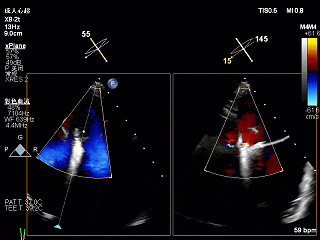

3D上彩确认夹子位置

2维上彩确认夹子位置

夹子关小后二维上彩,夹子两侧均有反流

夹子关紧后上彩

夹子关小后3D上彩

反流降至轻度

夹子释放后,2D下color,反流降至轻度

夹子释放后3D下观察组织桥稳定,反流降至trace

夹子释放后压差为2mmHg

肺静脉逆流明显改善